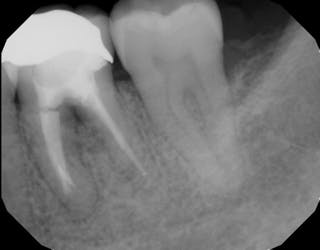

Periodontal Bone Loss Case Best Technique For Increasing Bone Height